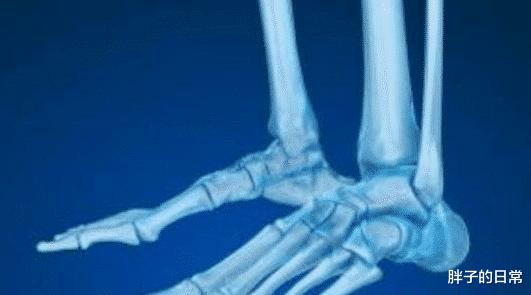

成年中国人的骨骼大概有204块 , 但是成年的西方人骨骼却一般是206块 , 这是在小时候骨骼发育后慢慢结合形成更加成熟的骨骼后的数量 , 但是为什么中西方人会有2块的差异呢?我们的骨骼又是哪里少了两块?

经过科学家们的研究 , 最后发现 , 原来在中国人与西方人的骨头对比上 , 缺少的那两块骨头是在小脚趾上面 , 中国人的小脚趾一般都是两节 , 而西方人的脚趾骨头是有三节 。 为什么会这样呢?很大的原因是在进化的过程中 , 人们环境的不同 , 西方人的身材更加高大 , 需要更多的脚趾骨来支撑自己的身体 。

专家们的推测就是中国人在进化中比较顺利 , 没有经历过什么挫折 , 基本上就顺顺利利的将脚趾上的那两节骨头融合 , 而西方人则不是 , 他们的进化要更艰难一些 , 所以小脚趾有三节 。 而中国人的骨头也并不是所有人都是两节 , 也有人发育的不完善的 , 就会有三节 。 而且其实这两块骨头的差异并没有什么特别大的影响 , 多度少少的 , 也没多大差别 。